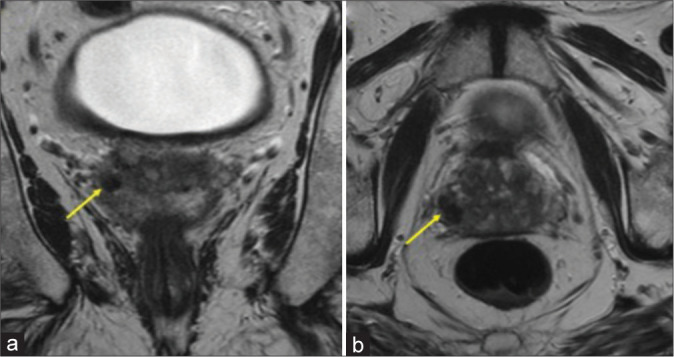

Granulomatous prostatitis (GP) is a rare form of chronic prostatitis with reported incidence of 0.65-1.5%. Radiological features of GP overlap with those of prostate adenocarcinoma. The following magnetic resonance imaging characteristics can suggest the diagnosis in an appropriate clinical setting: Diffuse or focal nodular low T2 signal, high signal on diffusion-weighted imaging with corresponding low apparent diffusion coefficient signal, and post-contrast imaging with lesion enhancement or rim-enhancing in the setting of caseous necrosis or abscess formation. Even with suspicion on imaging, the overlapping imaging features with prostate adenocarcinoma necessitate biopsy for confirmatory diagnosis. Here, we report a case of a 70-year-old man with GP in the setting of prior intravesicle bacillus Calmette-Guérin administration.